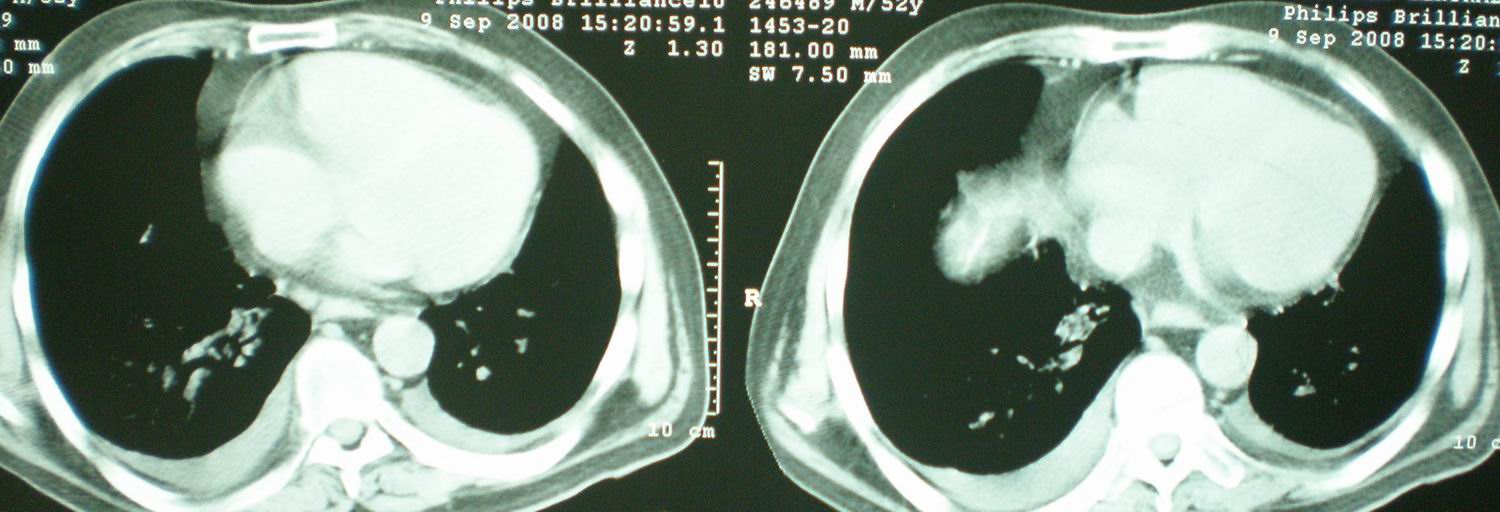

2008年9月18日ct片

2008年9月8日ct片: